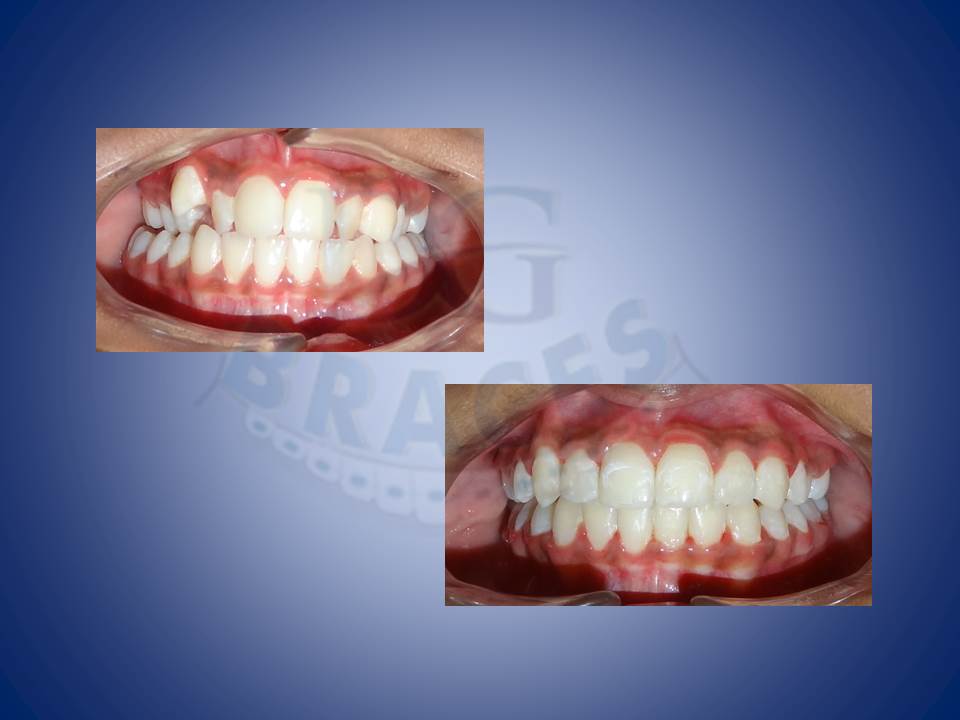

7.cross bites can be well corrected with rapid maxillary expansion using HYRAX for a stable and predictable results.